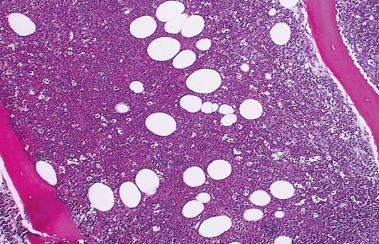

Normal

**Bone Marrow**

Hyperplastic

Hypoplastic